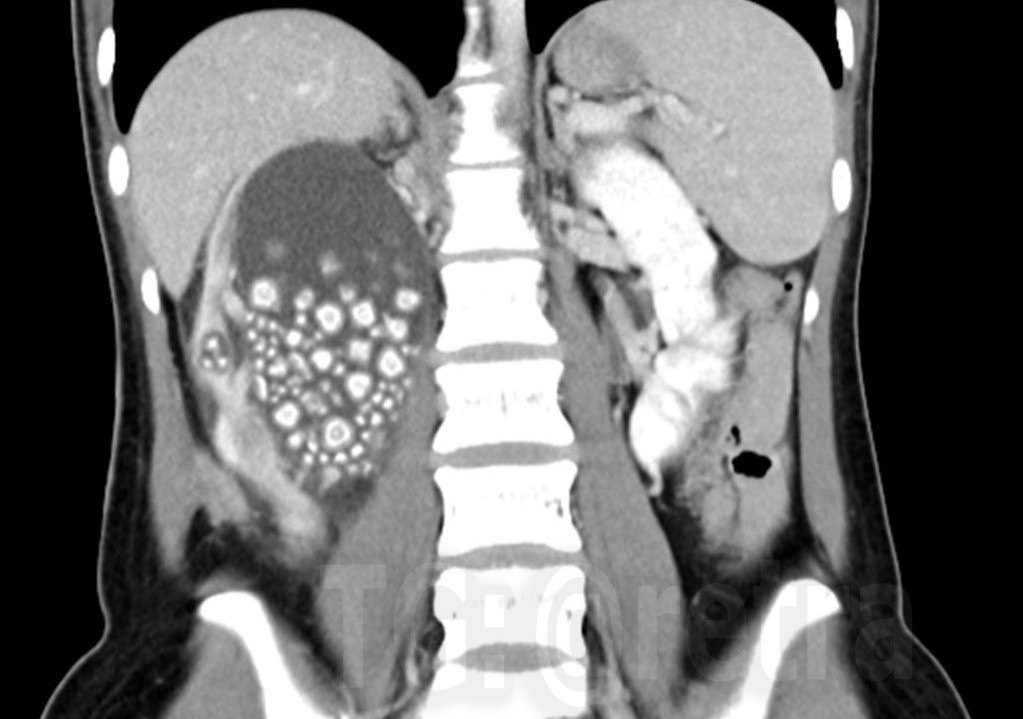

У 20-летней жительницы Тайваня удалили более 300 камней из почек из-за того, что она пила сладкие напитки, вместо воды

По словам СМИ, девушка постоянно пила холодный чай (бабл-ти) и соки, что привело к хроническому обезвоживанию и накоплению минералов в почках.

Из неё было удалено более 300 камней размером от 0,5 до 2 см.